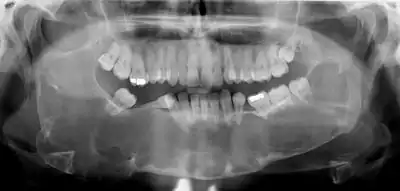

Radiographs of odontogenic keratocysts show well-defined radiolucent areas with rounded or scalloped margins which are well demarcated.[11] These areas can be multilocular or unilocular. The growth pattern of the lesion is very characteristic from which a diagnosis can be made as there is growth and spread both forward and backward along the medullary cavity with little expansion. No resorption of teeth or inferior dental canal and minimal displacement of teeth is seen. Due to lack of expansion of the odontogenic keratocyst, the lesion can be very large when radiographically discovered.[9]